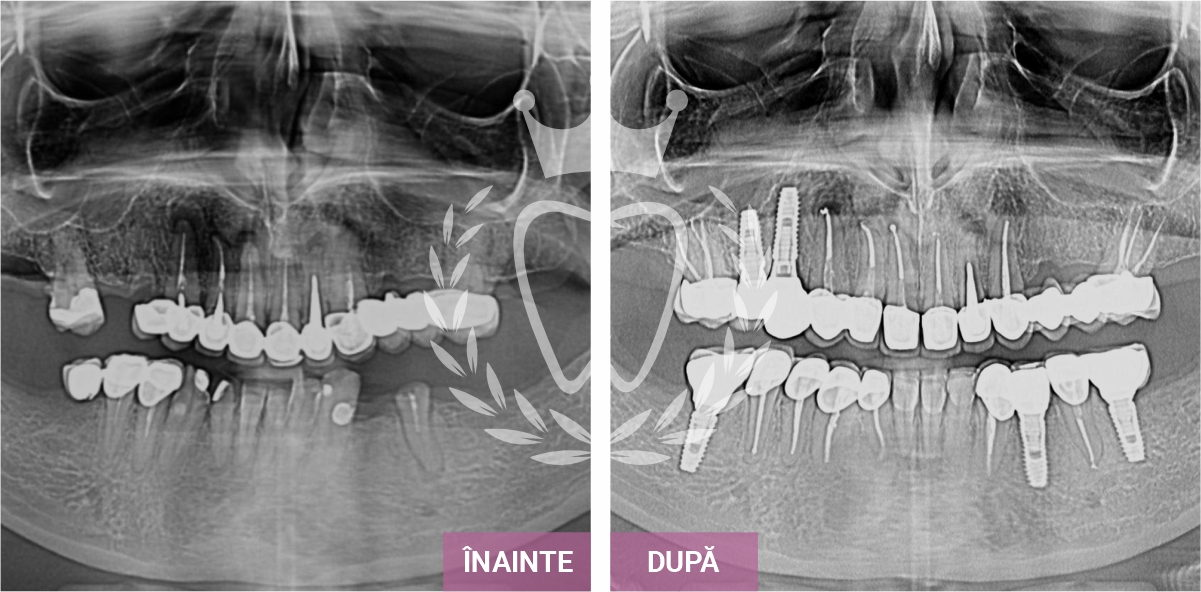

Îți prezentăm o selecție de cazuri care evidențiază rezultatele tratamentelor stomatologice realizate de echipa noastră.

De la implanturi dentare și tratamente ortodontice, până la endodonție, protetică și estetică dentară, fiecare caz reflectă grija, experiența și atenția oferită fiecărui pacient, pas cu pas.